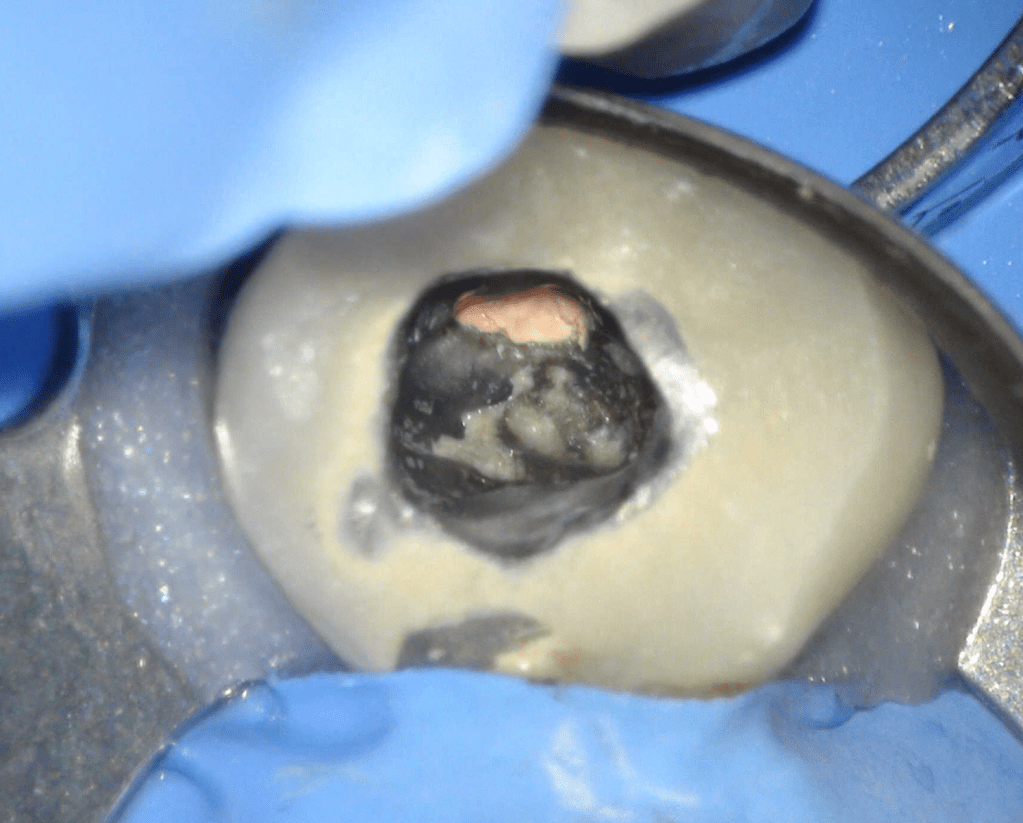

Reco pared vesticular